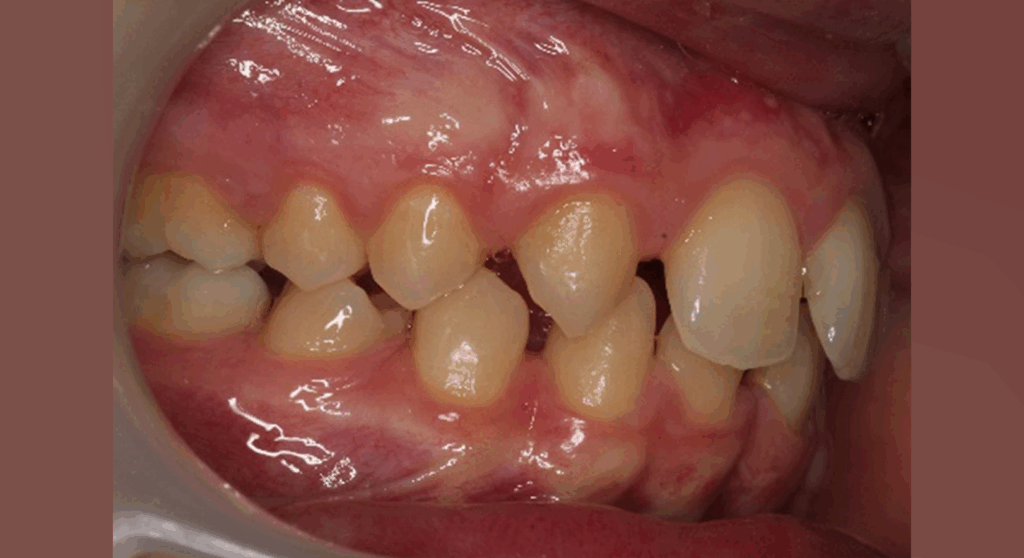

Skeletal Class II due to mandibular retrognathia, proclination of maxillary incisors, narrow arch creating a V-shaped arch, agenesis of 12, 31, 41, hyperdivergent facial pattern, moderate deep bite (2 mm), increased overjet (9 mm), asymmetric canine and molar Class II due to mandibular deviation to the left, maxillary midline deviation related to agenesis of 12, distal rotation of 35 and 45, and pronounced lower curve of Spee.

Elastics protocol

Class II elastics: 4.5 oz, 14 hours/day

Hooks on 13 and 23, button cut-outs on lower molars